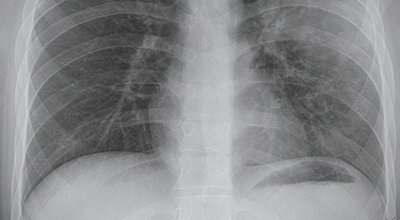

증상을 겪는 경우 배양 검사는 물론 X-ray 촬영 등을 통해 진단을 할 수 있어요. 필요한 경우 소변, 혈액, 혈청 검사, CT 등이 추가적으로 진행돼요.